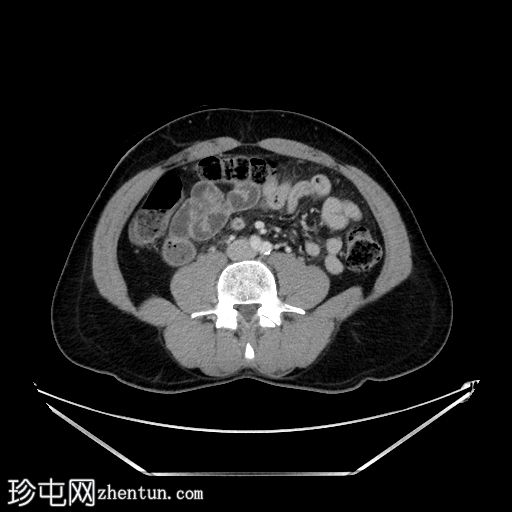

CT

轴位增强扫描(门静脉期)

阑尾扩张、增厚、强化,可见少量管腔外气体。右下腹及盆腔可见无序液体(伴有少量下垂钙化灶)及条索状改变。未见其他急性期征象。

本病例是阑尾炎早期穿孔的典型病例,仅可见少量管腔外气体,初次检查可能难以发现,且盆腔积液量较预期。盆腔内少量分层钙化灶可能是游离阑尾粪石,也可能是慢

性病

变(例如既往大网膜垂扭转所致)。